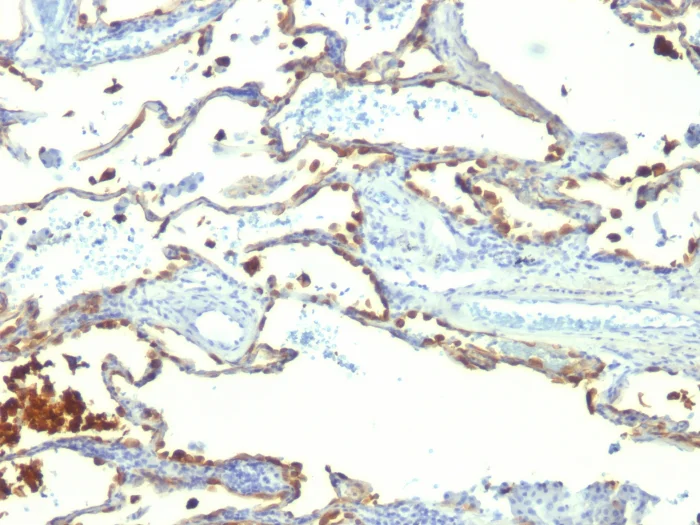

Immunohistochemistry (Formalin/PFA-fixed paraffin-embedded sections) - Anti-Milk Fat Globule 1 antibody [SPM291] (AB17787)

Immunohistochemical analysis of formalin-fixed, paraffin-embedded human lung carcinoma tissue labeling Milk Fat Globule 1 with ab18878 at 1 ug/ml.